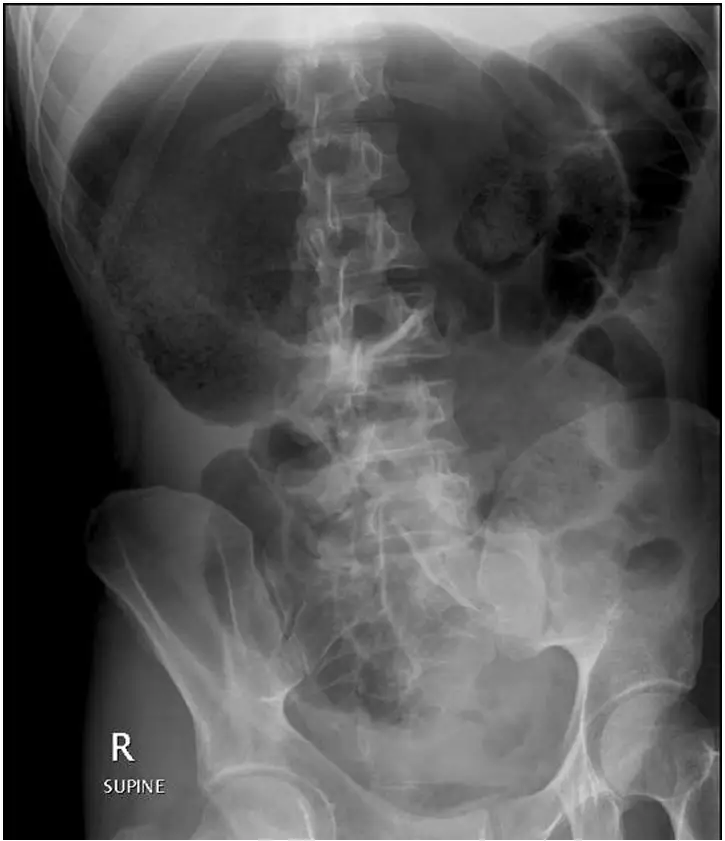

Esophageal Atresia X-ray: Radiographic Signs:

Esophageal Atresia X-ray: Other Cases: Radiological cases of Surgery It is a congenital condition that can be identified through radiographic findings. Key indicators include: What is Esophageal Atresia? It is a birth defect where a baby’s esophagus (food pipe) doesn’t connect properly to the stomach. Instead, it ends in a pouch, making swallowing impossible. This condition occurs […]